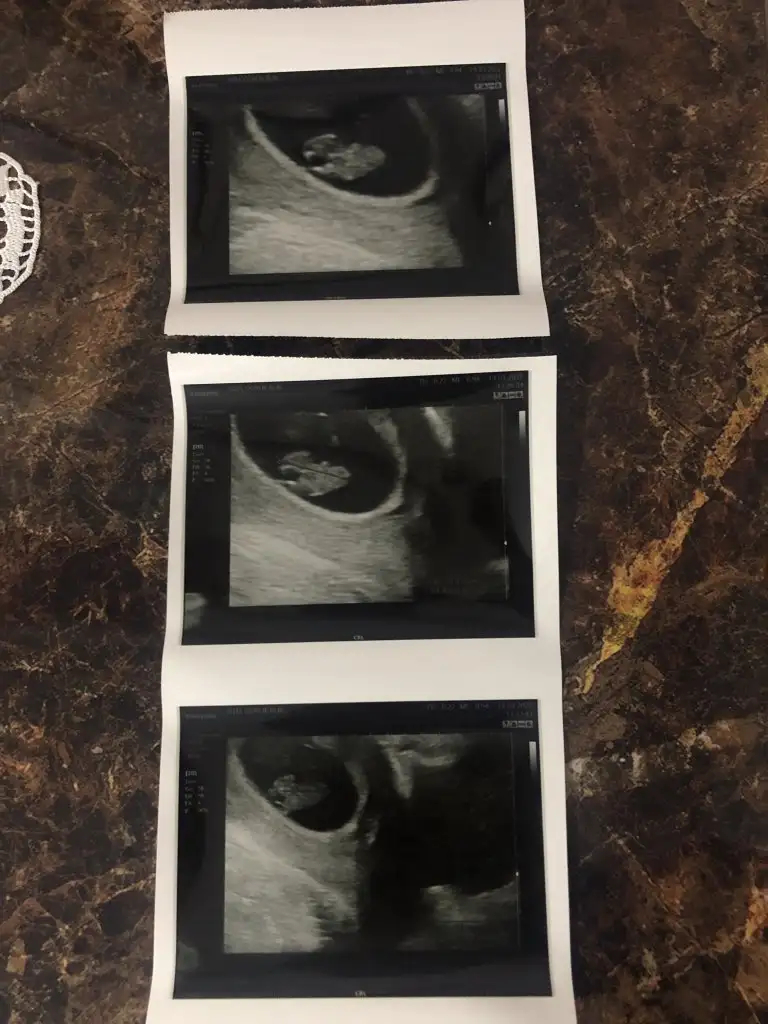

hayırlısı olsun benimde en son 8+5 resmim bu yeterki sağlıklı koşunlarda insan yine de merak ediyor teşekkür ederim